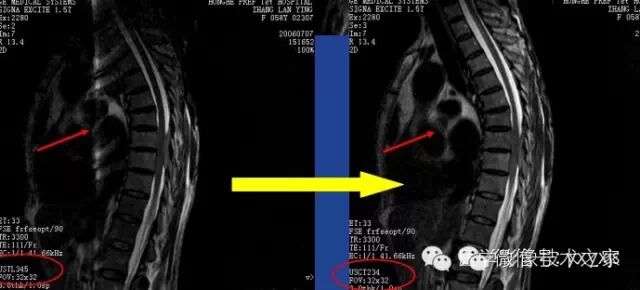

伪影特点:

相位编码方向出现的条带影或点状影。往往在脊柱扫描,选取线圈单元过多时出现。

解决办法:

扫描时启用符合扫描视野的线圈单元组合,不要启用过多。